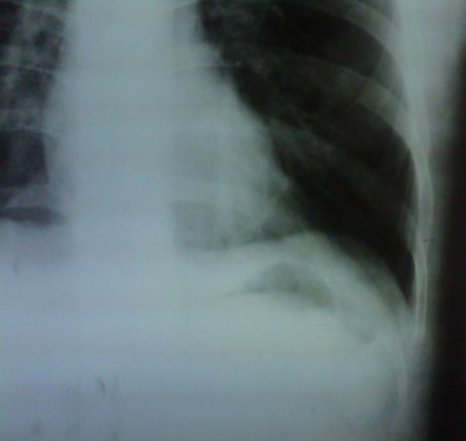

标题: X8070:考虑左侧肺底积液对吗???? [打印本页]

标题: X8070:考虑左侧肺底积液对吗????

男。20岁。咳嗽10天余。

左膈最高点偏外1/3,胃底与膈顶间距增大,不除我左肺底积液,建议变换体位(左侧倾斜60度)透视观察。

胃泡肺底间距增宽,超过2cm,提示左侧肺底积液。

膈肌外侧较高可提示肺底积液,结合透视观察。

胃泡膈顶间距增宽,但膈肌形态尚可,不支持肺底积液,不敢肯定,建议结合透视观察。